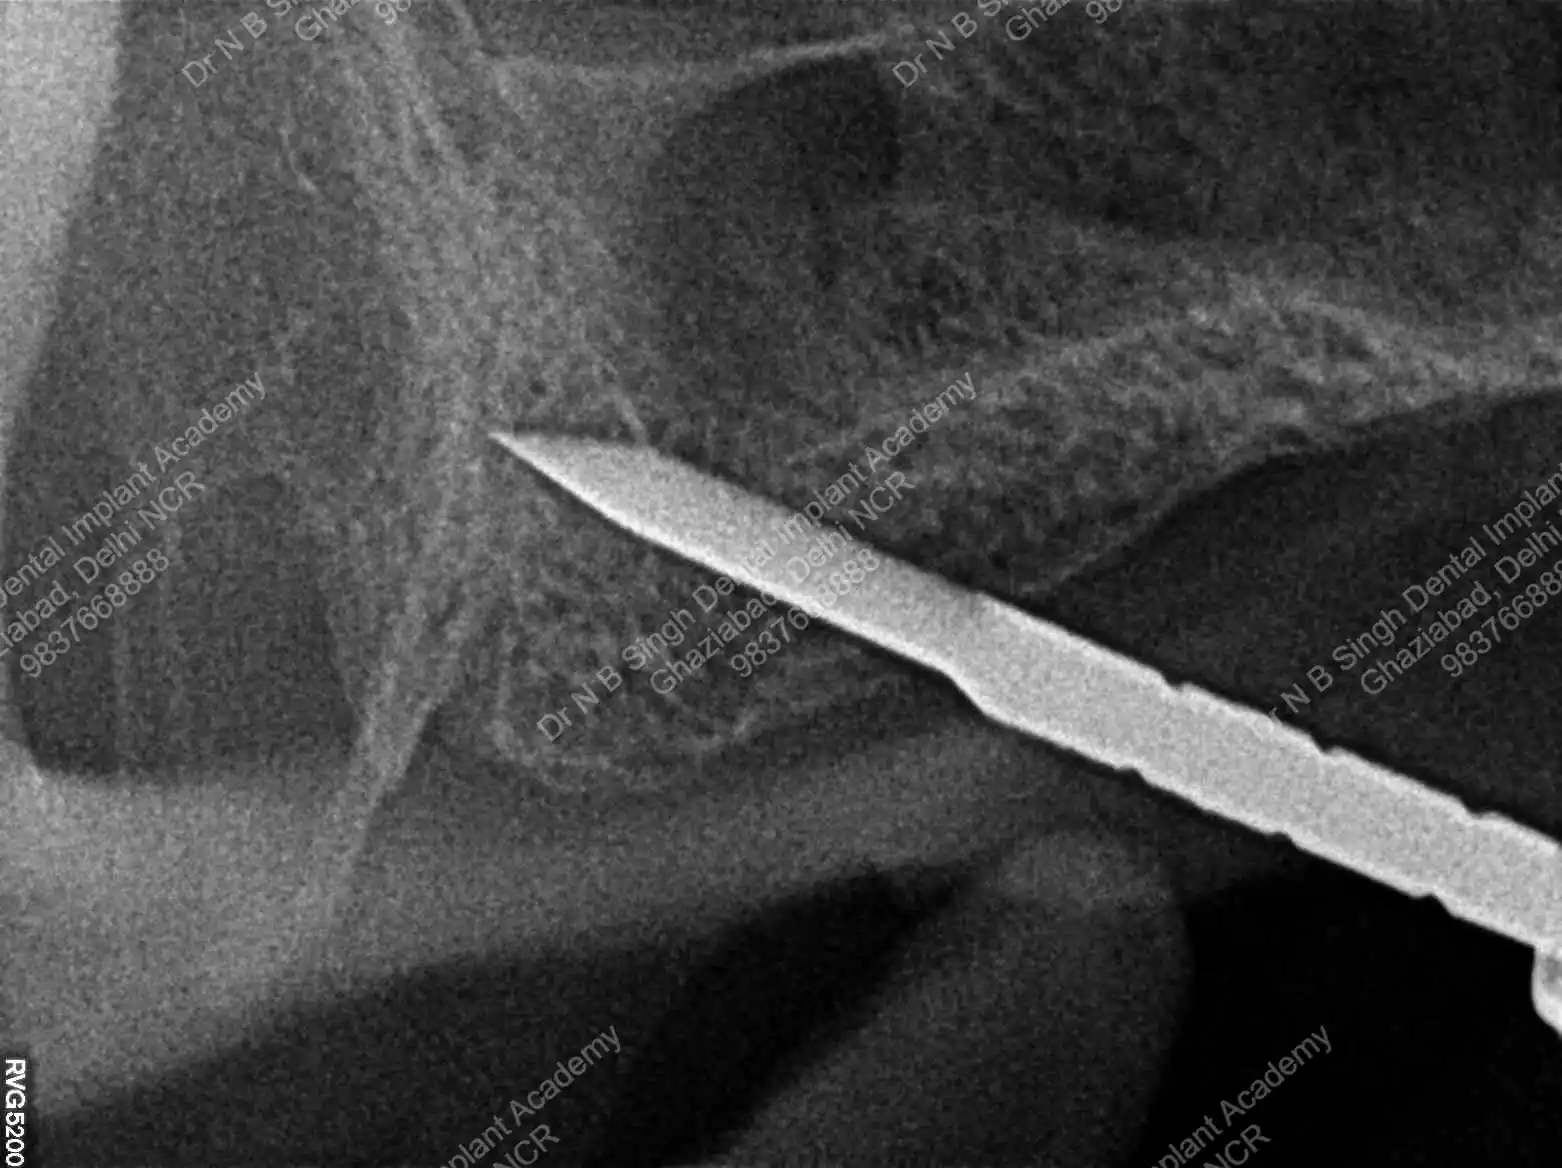

A008 Basal implants – af-qurs 1

Dr. N.B. Singh